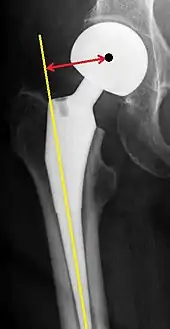

Post-operative projectional radiography is routinely performed to ensure proper configuration of hip prostheses.

The direction of the acetabular cup influences the range of motion of the leg, and also affects the risk of dislocation.[7] For this purpose, the acetabular inclination and the acetabular anteversion are measurements of cup angulation in the coronal plane and the sagittal plane, respectively.

Center of rotation: The horizontal center of rotation is calculated as the distance between the acetabular teardrop and the center of the head (or caput) of the prosthesis and/or the native femoral head on the contralateral side.[69] The vertical center of rotation instead uses the transischial line for reference.[69] The parameter should be equal on both sides.[69]